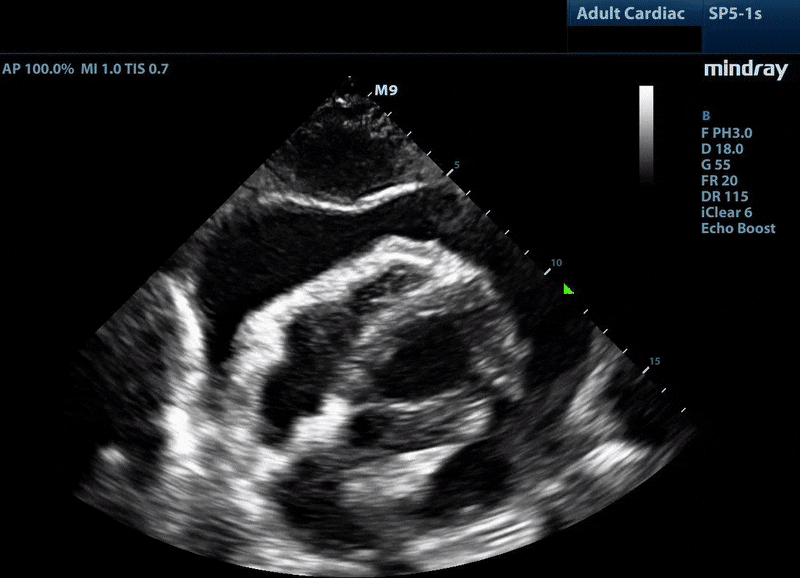

Name of this ultrasound finding of the heart.

What is a cardiac myxoma?

Name the EKG finding associated with this US finding.

What is electrical alternans?